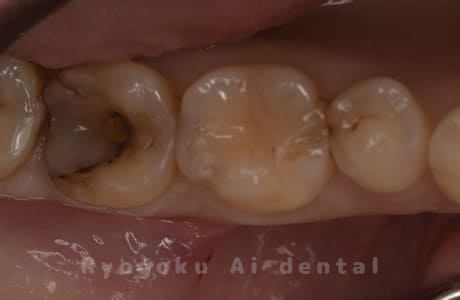

Case05

- 重度カリエス

- 治療内容

- ジルコニアクラウン

- 治療費用

- 165,000円

他院で治療終了と言われ、転院された患者様です。土台を外し、土台をやり変え、ジルコニアクラウンで型取りを行いました。

<リスク・副作用>

過度の咬合や衝撃で割れることがあります。